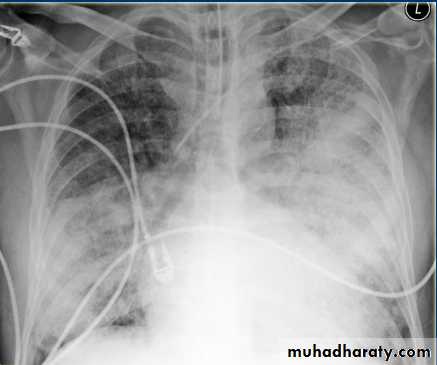

CT lung cavityPulmonary collapse(atelectasis): loss of volume of a lobe or lung, common causes: bronchial obst., pneumothorax or pl. effusion, linear(discoid) atelectasis.

Collapse caused by bronchial obst.: occurs due to air can not get into the lung in sufficient amount to replace the air absorbed from alveoli.

Signs of lobar collapse:

1- displacement of structures

2- shadow of collapsed lobe/ consolidation, almost invariably accompanies lobar collapse.

3- Silhouette sign: A- help to dx. Lobar collapse when resulting shadow is difficult to appreciated. B- decide which lobe is collapsed.

Collapse of ant. Located lobes, upper and middle, obliterate portions of med. And heart outlines, whereas collapse of lower lobes obscure diaph. And descending aorta.

When lobe collapse, the unabsorbed lobe(s) on the side of collapse undergo compensatory expansion, the displaced fissure seen as well defined boundary to airless lobe, the med. And diaph. May move towards collapsed lobe.

With collapse of whole one lung, the entire hemithorax is opaque, and there is substantial med. And tracheal shift.